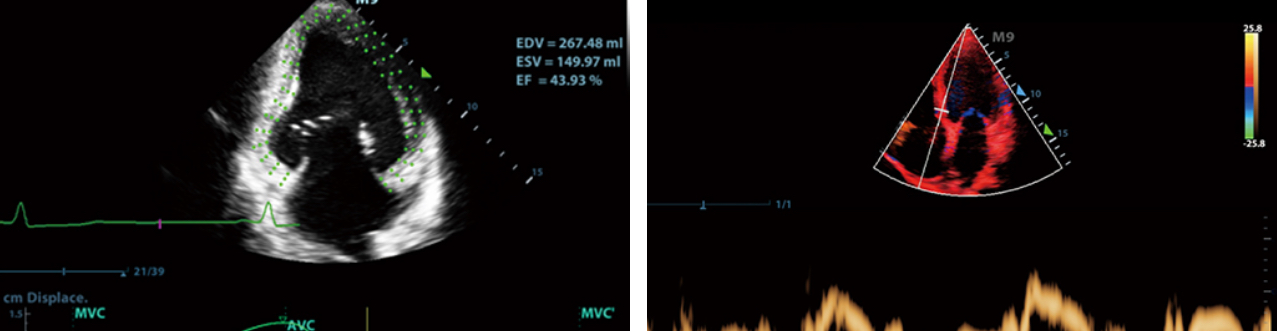

- 4. Para el inicio de la enfermedad cardĂaca, apoya la mediciĂłn automĂĄtica de la funciĂłn cardĂaca, la evaluaciĂłn Doppler tisular de la funciĂłn diastĂłlica de TDI, la evaluaciĂłn del seguimiento de la mancha de tejido del movimiento de la mĂĄquina cardĂaca, etc.